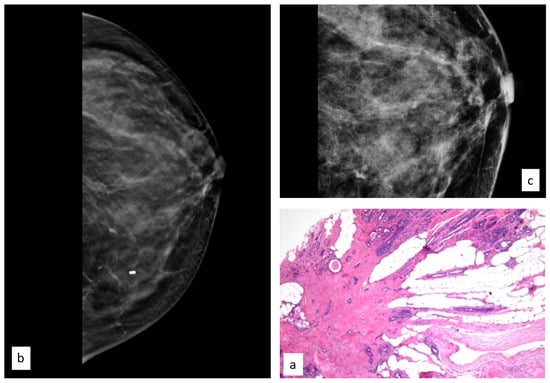

The initial radiological findings were 114 microcalcifications, 84 masses, and two architectural distortions; the mean radiological suspicion level was BIRADS 4 (range 3–5). Illustrative radiologic and histologic examples of ADH are shown in Figure 4.

Figure 4.

Histologic picture (a, Magnification (×20)) and radiological presentation ((b) right MLO view; (c) magnification) of atypical ductal hyperplasia (white circle).

Of the 200 ADH patients, 27 (13.6%) developed subsequent breast cancer during follow-up, 18 (66.6%) in the same breast as the ADH and 9 (33.3%) in the contralateral breast.

The median time interval from first diagnosis of a B3 lesion to subsequent diagnosis of BC was 32 months.